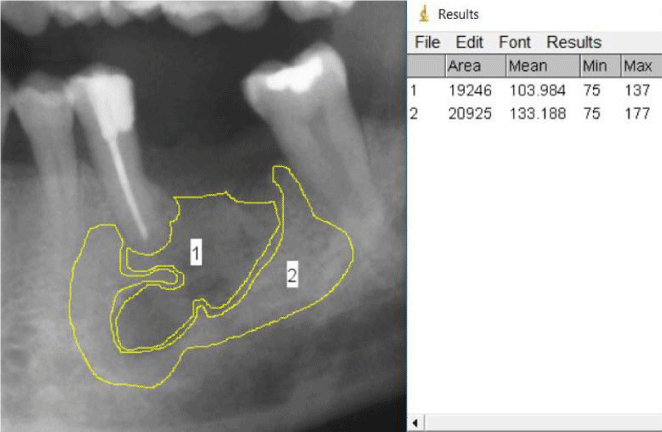

Figures 1 and 2 show examples for the selection of the regions of interest and the measurement process in the lower jaw in a postoperative and a control radiograph.

Figure 1: Amplified detail of case 4: ROI 1 representing the defect region, ROI 2 representing the surrounding cancellous bone. On the right hand the results of the measurements are shown.

The first impression of the workgroup was that the method was generally easy to apply on the selected cases and did not presume a lot of training or technical know-how. The software was easy to handle and the results are presented in worksheets which allow direct input to statistical analysis. Figures 1 and 2 show amplified details of case 4 and its follow up (case 9) with the Regions of Interest formed by using the SOP by rater 1 as well as some measuring examples. Table 2 shows the results of the measurements of the different members of the workgroup and the corresponding coefficient of variation.